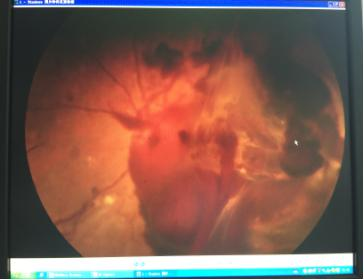

突然出现无痛性视力丧失,或突然出现眼前黑点、蜘蛛网或烟雾,这或许就是我们通常说的玻璃体出血,玻璃体从透明变成暗红色的球体,无法窥到眼底,可是玻璃体本身没有血管,如此滔滔出血从何而来?

玻 璃体是眼球结构的一部分,它参与构成屈光间质,它的容积占眼球的4.5 mml。玻璃体的出血是指玻璃体周围的组织血管病变出血,流入玻璃体内,造成玻璃体积血,使屈光间质变得不透明,导致视力下降或丧失,如果不治疗可能并发 新生血管性青光眼导致失明。它可以由眼内血管性疾患和损伤引起,也可以由于全身性疾患引起,如糖尿病、高血压等。

(1)严重的玻璃体积血 眼底红光反射消失,无法看到眼底。裂隙灯下可见前玻璃体红细胞。(2)轻度玻璃体积血 可见出血遮挡部分视网膜或视网膜血管。(3)慢性玻璃体积血 因血红蛋白降解而呈赭黄色玻璃体混浊。